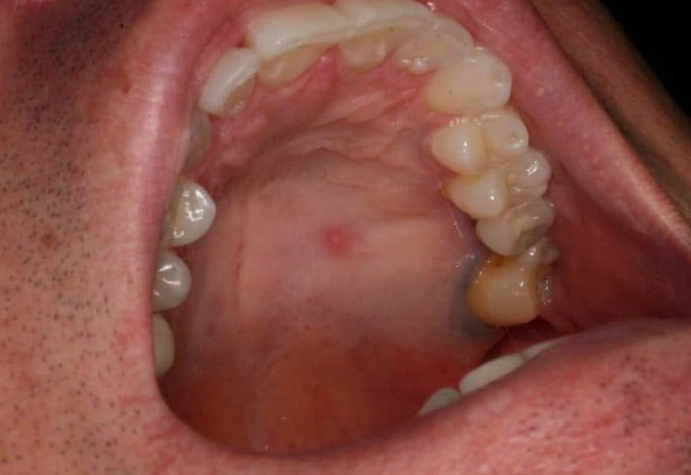

- Palatal Torus / Mandibular Torus: This was my personal mystery lump. A torus is a slow-growing, bony protrusion. A palatal torus is a hard, bony lump in the middle of the roof of the mouth. A mandibular torus is on the inside of the lower jaw, near the premolars. They feel like solid rock—because they are bone. They're genetic, harmless, and only need removal if they interfere with dentures.